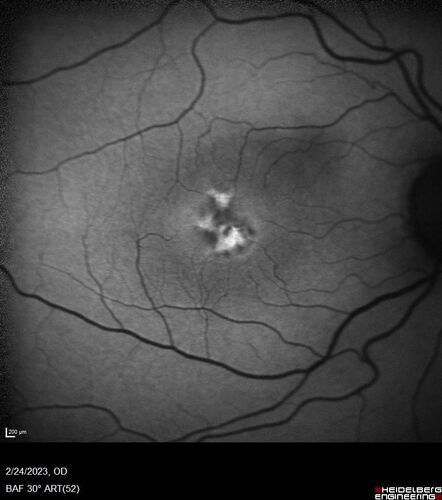

Pattern Dystrophy - PHPR2 Gene

57 year old man- VA 20/25 OD, 20/20 OS - Many family members have retinitis pigmentosa

Pattern Dystrophy - PHPR2 - RP in Family